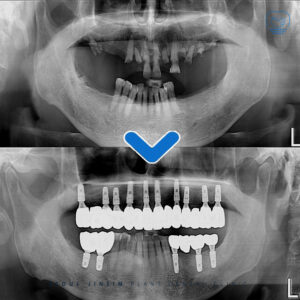

수원정자동임플란트 다수치 발치 후 전악 임플란트 . 안녕하세요 수원 정자동에 위치하고 있는 서울진심플란트치과입니다. . 오늘은 수원정자동임플란트 진행하신 환자분 사례를 소개하고자 합니다. . 위의 파노라마 사진이 수원정자동치과 처음 방문하셨던 환자분의 파노라마입니다.…